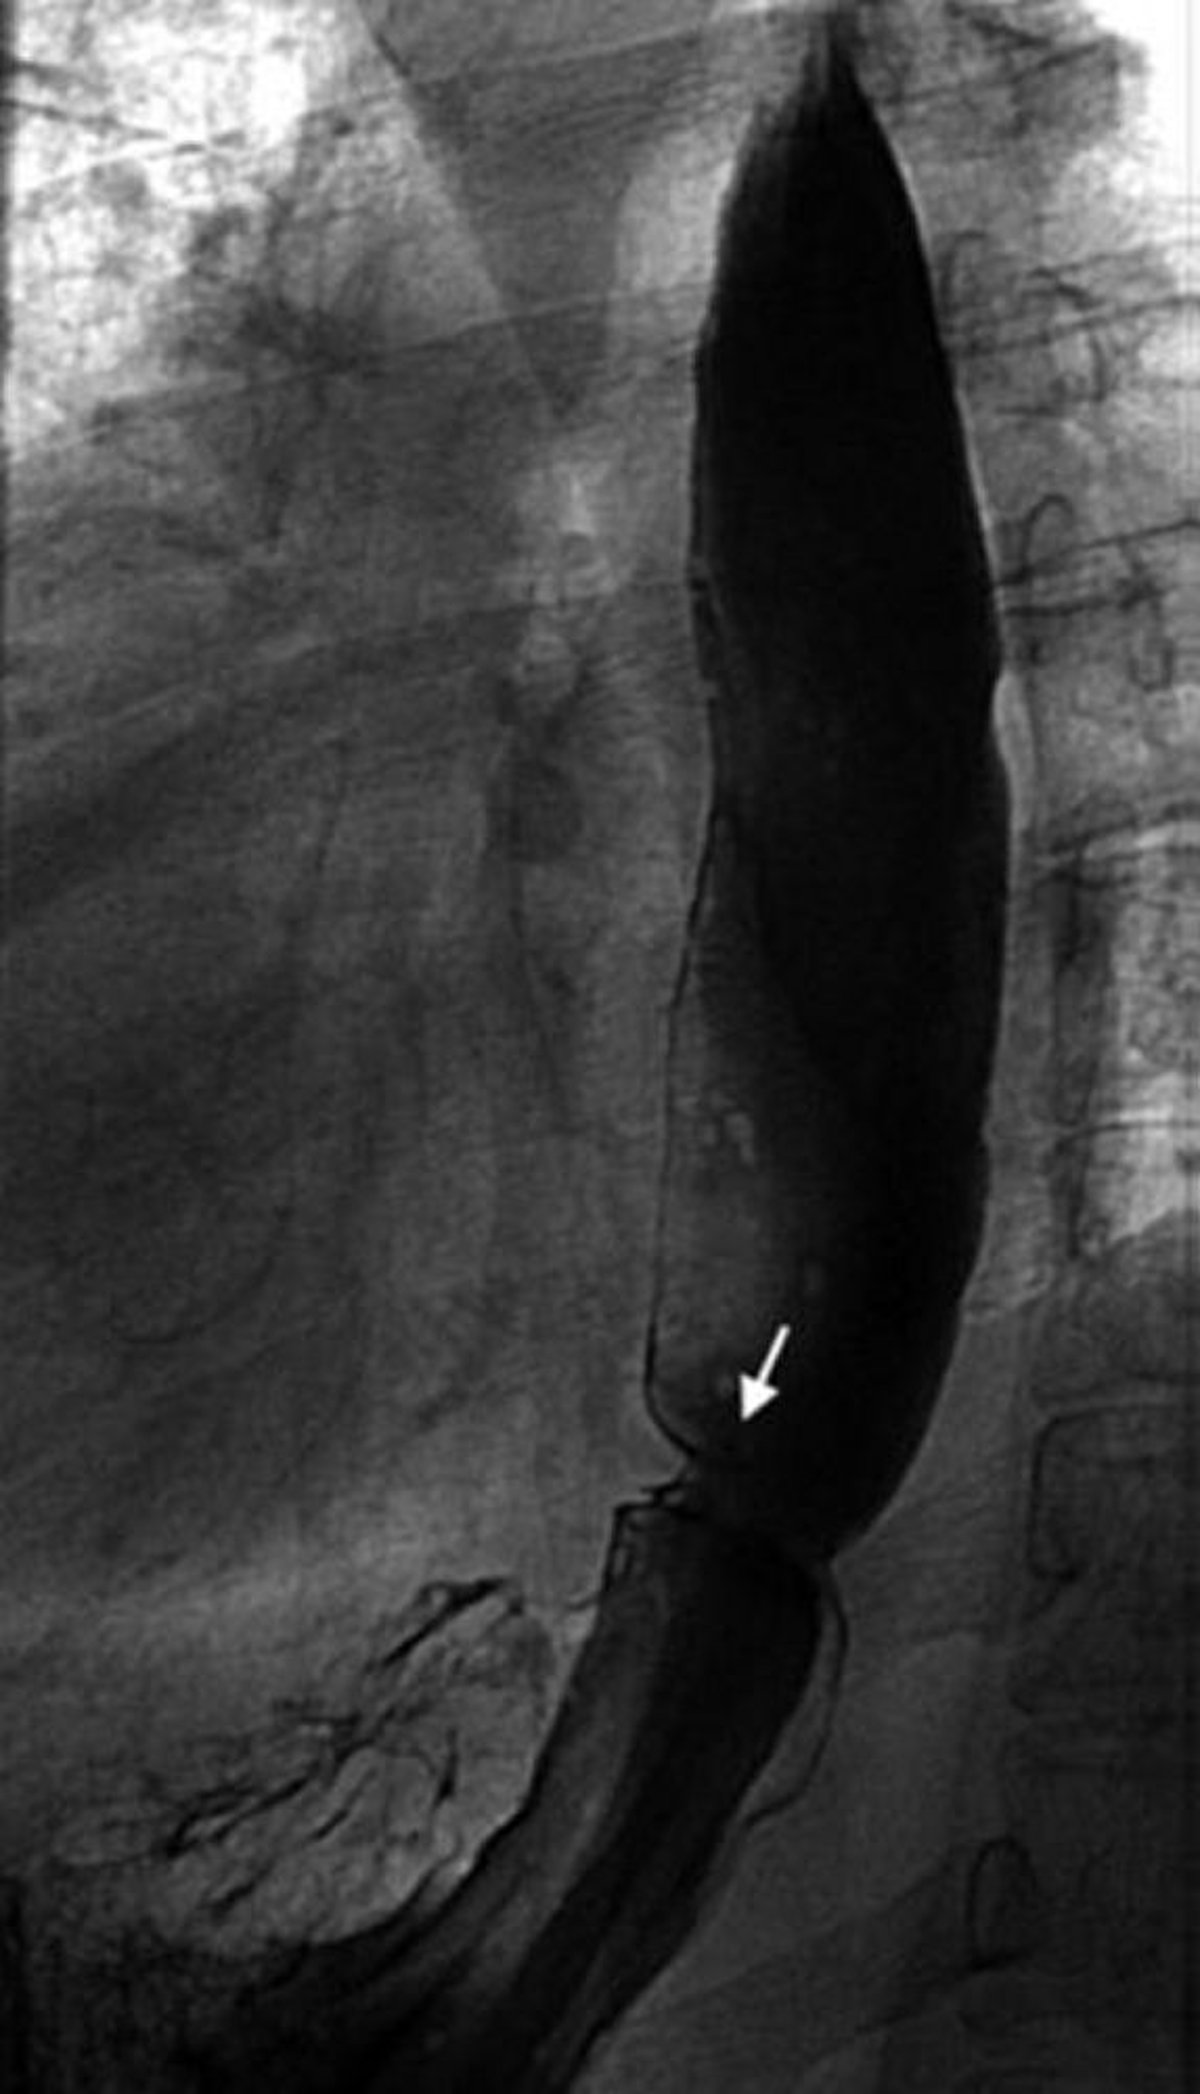

Trago de bario que muestra un anillo esofágico

Esta imagen muestra un anillo de Schatzki (flecha).

Anillo esofágico inferior